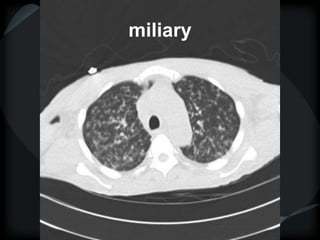

miliary

random